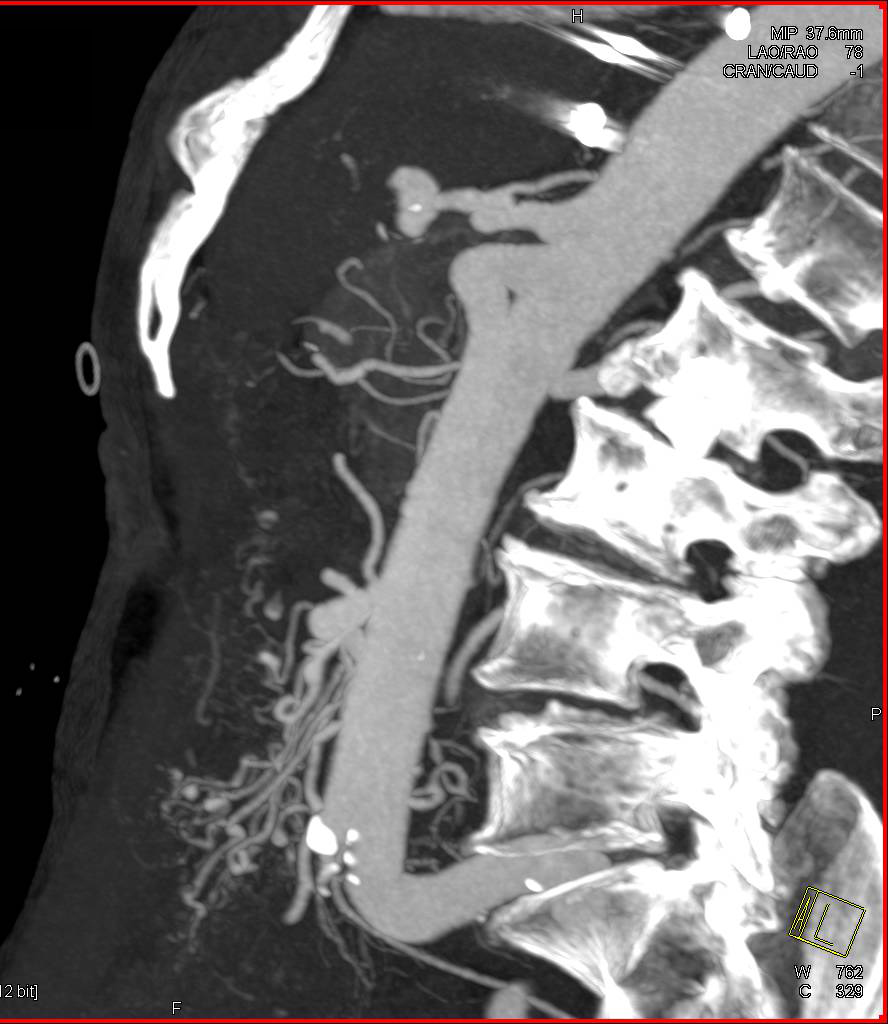

Sclerosing Mesenteritis with Calcified Mesenteric Mass